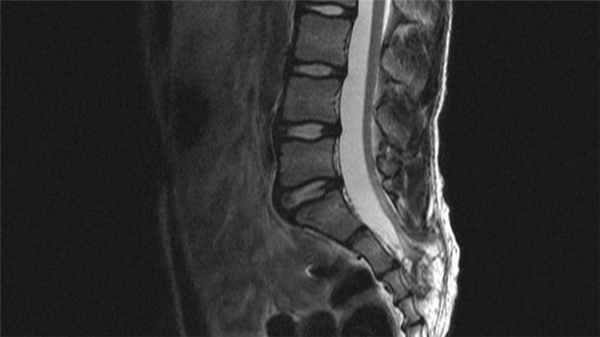

МРТ поясничного отдела позвоночника. Т2-взвешенная сагиттальная МРТ. Spina bifida и менингоцеле. Цветовая обработка изображения.

Костные аномалии позвоночного столба, встречающиеся у большинства пациентов с синдромом фиксированного спинного мозга, и включают различные варианты расщепленного позвонка, количественные и качественные дефекты дуг и тел, сакральную агенезию, и в редких случаях синдром каудальной регрессии. Главным методом диагностики фиксированного конского хвоста является МРТ поясничного отдела позвоночника, оно позволяет выявить все варианты аномалий развития позвоночника, включая липомиелоцеле и фибролипому. При МРТ в СПб в наших клиниках при наличии аномалий мы рекомендуем комплексное МРТ исследование головного мозга, МРТ позвоночника и спинного мозга. Опыт показывает, что МРТ СПб при аномалиях развития лучше делать в центрах с большим подобным опытом, как у нас.

«Золотым стандартом» диагностики позвоночника и спинного мозга является магнитно – резонансная томография (МРТ), позволяющая определить анатомо–морфологические взаимоотношения в сложной анатомической системе «спинной мозг - позвоночный канал - мягкие ткани, выявить скрытые формы спинальных пороков и уточнить прямые и косвенные признаки «фиксации спинного мозга». Патогномоничный симптом синдрома фиксированного спинного мозга — опущение конуса спинного мозга ниже L1 – L2 позвонка, с признаками утолщения конечной нити.